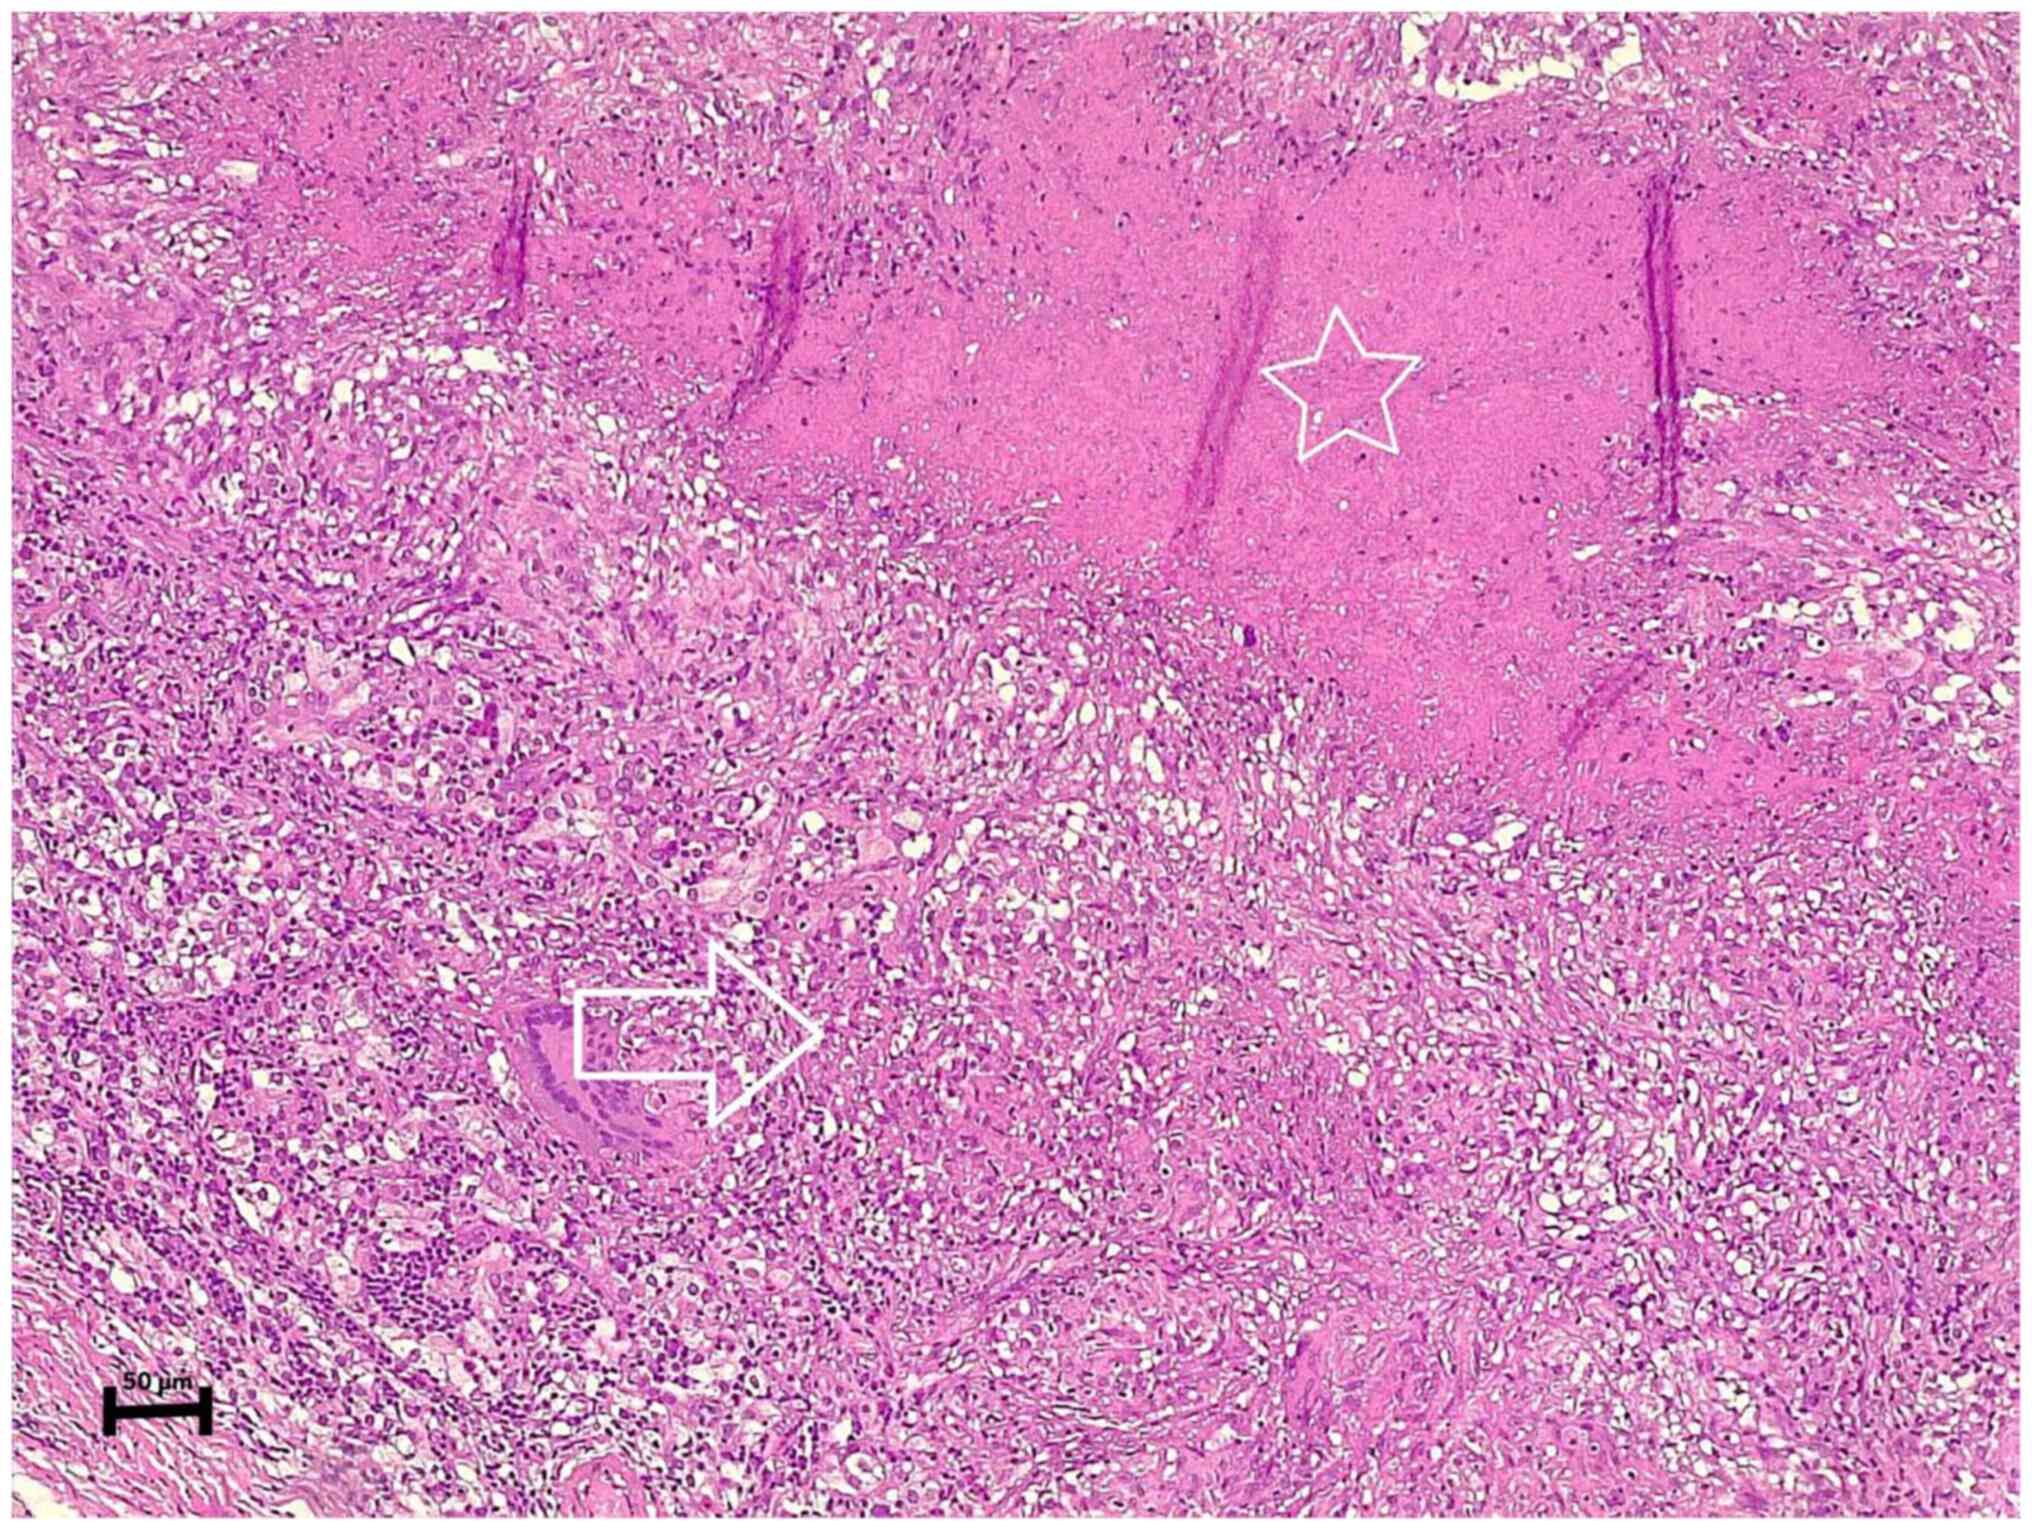

After proceeding to the left thyroid lobectomy and excising the left parathyroid gland, the histopathological examination revealed a parathyroid adenoma with caseating granulomatous inflammation involving the adenoma, suggestive of TB (Fig. 2). In addition, the left thyroid gland exhibited a nodular goiter with focal lymphocytic thyroiditis.

Figure 2

The section of the specimen (stained with eosin and hematoxylin) under microscopy illustrates a parathyroid adenoma containing well-defined epithelioid granulomas (arrow) with areas of caseating necrosis (star).

The histopathological examination was performed by the authors' laboratory as follows: The sections (4-µm-thick) were paraffin-embedded and fixed with 10% neutral buffered formalin at room temperature for 24 h. They were subsequently stained with hematoxylin and eosin (Bio Optica Co.) for 1-2 min at room temperature and then examined under a light microscope (Leica Microsystems GmbH).